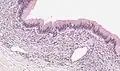

PRMC and benign mucinous cystadenoma of the ovary are microscopically similar. Both are multiloculated cystic neoplasms and are lined by a single layer of tall columnar cells with a clear basal nucleus and cytoplasm. Both of them have identical histochemical and ultrastructural features.[9] Flat to low cuboidal cells, resembling mesothelial cells, in the lining interspersed between columnar cells in the same area is the only histological difference between the two tumors.[9]